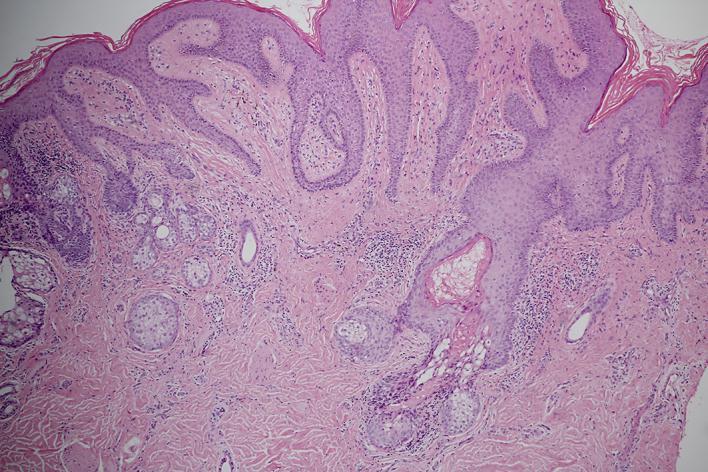

Nevus sebaceous is a congenital, benign hamartomatous lesion, characterized by a yellowish to skin-colored, hairless, verrucous plaque on the head and neck region. In later life, a secondary tumor, either benign or malignant, can develop within nevus sebaceous. Eccrine poroma developing on nevus sebaceous is extremely rare. There are few case reports of eccrine poroma developing within nevus sebaceous. We report a case of a 30-year-old female who presented with a congenital, hairless, verrucous, yellowish lesion on the scalp and an erythematous nodule arising within the yellowish lesion for 8 months. Her clinical presentation and histopathological findings were compatible with nevus sebaceous and eccrine poroma.

皮脂腺痣是一种先天性良性错构瘤性病变,其特征为头颈部出现淡黄色至肤色、无毛的疣状斑块。在后期生活中,皮脂腺痣内可发生良性或恶性的继发性肿瘤。发生于皮脂腺痣的小汗腺汗孔瘤极为罕见。关于皮脂腺痣内发生小汗腺汗孔瘤的病例报告很少。我们报告一例30岁女性,其头皮有一先天性、无毛、疣状、淡黄色病变,且在该淡黄色病变内出现一红色结节8个月。她的临床表现和组织病理学检查结果符合皮脂腺痣和小汗腺汗孔瘤。